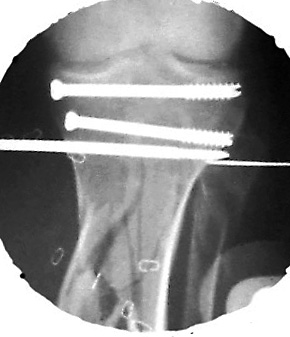

Date: Thu, 14 Dec 1995 17:48:46From: hwb@eideti.com (Bill Burman)Of course what I have to say has to be taken with a mountain of salt as Ihave not practiced orthopaedics for 5 years.What I would do at this point is hike out the 5 mm diaphyseal pin. I can'tbelieve it is doing much. I would wait a few more weeks for that pin tractto properly clean itself and seal up. Hopefully it has not been infected.At that time I ought to have pretty good consolidation of themetaphyseal-epiphyseal fractures. I would remove from the ends of the boneany hardware which would block the placement of a reamed interlockingtibial nail. Large reduction forceps and possibly strategically placedsteinman pins would be used to protect against the possibilty ofmetaphyseal-epiphyseal refracture during nail placement. The nail needs tobe carefully started as high as possible and more lateral than usualbecause of a valgus tendency for nailings of proximal tibia fxs.If at this time, I did not see much in the way of diaphyseal callus thenprior to nail placement, I would try to do a closed intramedullary iliacbone grafting with chest tube ala Chapman, JBJS 62A 1004 1980. I realizethis technique was meant for segmental defects of the femur but this mightbe an application for it as well. If I couldn't get much graft in this way,I would put it in posterolateral - if that did not jeopardize the free flapin some way.*****************************From: EDCCYANG@aol.comDate: Thu, 14 Dec 1995 22:16:30 -0500You are to be commended for what you've done so far. It sounds like thetibia is well aligned and the soft tissues are healed. Now you just have toget the bones healed.I have extensive experience with the hybrid exfix but never have I seen atibia this shattered. (or maybe once)Now I would try the exogen unit, if you have not done so already. This isthe ultrasound device which has been working great for us! Their telephone# is 1-800-836-0849.I would hold him in the external fixator as long as the pins are clean.Hopefully, some of the fractures will heal and you can deal with only one ortwo nonunion sites. Consider plating the fibula and getting the fibulahealed, either simultaneously with a fib-pro-tib operation, and /orposterolateral bone graft. I have done all of the above to get tibiae toheal.Edward Yang, MDElmhurst HospitalMount Sinai****************Date: Fri, 15 Dec 1995 10:21From: Jeffrey Anglen Bill, for a guy who hasn't practiced clinically for 5 years, you seem tohave a pretty good grip on treating tibia fractures. The only thing I woulddisagree with is conversion to an intramedullary nail after this period oftime. I would be too afraid of intramedullary infection from a pin site,even if the pin sites looked OK. I don't know if the risk is the same withhybrid fixators as it is with traditional half-pin fixators - that might makean interesting study - perhaps someone with more experience withhybrid fixators has a better feel for the relative risk between pin andwire sites.I would continue with hybrid fixation, a little weightbearing and earlybone graft of the diaphysis posterolaterally. I have no experience withthe accordion technique.How about you guys at Harborview? Any thoughts on this tibiafracture?****************Date: Sat, 16 Dec 1995 11:45:10 +0530 (IST)From: "Dr.ML Parihar" the accordion manouevre does not work. to my knowledge this is nowuniversally accepted, especially in the treatment of non-unions. anyonedisagree?for a comminuted fracture of the tibia why not consider atibia-pro-fibula grafting as described by harmon. while on the subject ofbone grafting i would like to hear fromsurgeons who have used bone marrowinjections for the treatment of nonunion or delayed union.how much to be aspirated? from where?where do you inject? into the fracture site or in a cuff fashion aroundthe fracture site? Dr. Mangal Parihar**************************Date: Sat, 16 Dec 95 22:04:09 +0500From: "Alexander N. Chelnokov" Hi> I have not received any further comments/suggestions on the comminuted> tibia case since posting the images of the xrays. There has been> considerable useful discussion of posting images to be easily viewed> in various manners.Sorry but I missed when you pointed the name and location of the image so plsrepeat...> I did institute the "accordion" technique of .25 mm compression at> 6 am and noon; then .25 distraction at 6 pm and midnite.We use another schedule - 2 weeks of distraction 0.5mm/day and then2 weeks of compression 1 mm/day...> I also started 10 pound weight bearing.I do not limit weigth-bearing. More exactly, patient should load his legas he can. In case of extra-articular fractures of course.> I'd like to bone graft it but I'm not sure> where to put the bone graft because there are so many pieces.Do think about marginal corticotomy and slow tension of fragments to bridgegaps?*************************Date: Sun, 17 Dec 95 21:45:18 -0600From: "Andrew H. Schmidt" After seeing the images, I congratulate Tom on his management of the casethus far. Our general philosophy at Hennepin County is that once externalfixation is chosen as the treatment, it should be continued to union. Whenpossible, we will convert to a nail within the first couple of weeks, butnot beyond this because of the concern for infection.In my experience with either plateau or plafond fractures plus diaphysealextension, the metaphyseal fractures heal and it is the diaphysealcomponent that requires grafting. I have several times removed the hybridfixator, curretted the pin sites, performed an open autogenous grafting,and reapplied a new half-plane unilateral fixator to the diaphysis. Ofcourse, if the hybrid frame was still needed I would not replace it.However, I find the circular hybrid frames to be such a hassle to take careof, and the patients dislike them so much, that if the juxta-articularfractures are healed, I go ahead and convert to a simpler fixator. So, that remains my two-cents worth, which I thought I'd post to the wholegroup this time since this case has sparked so much interest.AndyAndrew H. Schmidt, M.D.Staff Physician, Hennepin County Medical CenterClinical Instructor, University of Minnesota******************************Date: Tue, 19 Dec 1995 12:31:57 -0500From: hwb@eideti.com (Bill Burman) I see from the discussion that perhaps I am too aggressive and need tolearn how to relax.I am learning some new things here. Dr. Ed Yang made a plug for ultrasoundstimulation - Exogen. Here is the abstract of an article published in theJ Bone Joint Surg Am 1994 Jan;76(1):26-34 by the San Antonio group(Heckman, Ryaby, McCabe J, Frey JJ, Kilcoyne RF). The study was paid forby Exogen.TI - "Acceleration of tibial fracture-healing by non-invasive, low-intensity pulsed ultrasound."AB - "Sixty-seven closed or grade-I open fractures of the tibial shaft were examined in a prospective, randomized, double-blind evaluation of use of a new ultrasound stimulating device as an adjunct to conventional treatment with a cast. Thirty-three fractures were treated with the active device and thirty-four, with a placebo control device. At the end of the treatment, there was a statistically significant decrease in the time to clinical healing (86 +/- 5.8 days in the active-treatment group compared with 114 +/- 10.4 days in the control group) (p = 0.01) and also a significant decrease in the time to over-all (clinical and radiographic) healing (96 +/- 4.9 days in the active-treatment group compared with 154 +/- 13.7 days in the control group) (p = 0.0001). The patients' compliance with the use of the device was excellent, and there were no serious complications related to its use. This study confirms earlier animal and clinical studies that demonstrated the efficacy of low-intensity ultrasound stimulation in the acceleration of the normal fracture-repair process."Also, Dr. Parihar mentions bone marrow injection. In CORR 313 8-18, 1995,Dr. John Conolly of Orlando, FL writes :TI - "Injectable Bone Marrow Preparations to Stimulate Osteogenic Repair."AB - "The great versatility of bone marrow transplants based on stem cellactivity has been demonstrated successfully for a variety of previouslyuntreatable hemopoetic conditions. Autologous bone marrow delivered bypercutaneous injection or by a direct transplant as a composite graft alsohas proven effective for osteogenic stimulation in a series of 100 skeletalhealing problems, including delayed unions and nonunions of fractures,arthrodeses, and bone defects. The efficiency of marrow to form bone can beincreased by a number of methods, including differential centrifugation andcomposite grafts of marrow with demineralized bone matrix and othercarriers or stimulatory factors."Dr. Connolly concludes his article by saying :"Marrow and marrow composite grafts, in this author's experience during thepast 8 years, essentially have eliminated the need for open harvesting anddelivery of autologous bone grafts to stimulate osteogenic repair ofdelayed unions, nonunions, arthrodeses and bone defects."Any references for the Ilizarov "accordion maneuver"?***************************Date: Tue, 19 Dec 1995 14:11:27From: hwb@eideti.com (Bill Burman)I am transmitting another opinion received via the HWB BBS fromDr. Joldas KuldjanovVisiting Professor at Detroit Medical CenterProfessor of Orthopedics & TraumaUniversity of Tashkent, UzbekistanRe: comminuted tibia fxThus far, there appears to be no sign healing because of local factors, thehigh energy of trauma, stripping of periosteum, soft tissue damage and poorcontact of bone. I would have initially fixed the fracture with a four ringIlizarov fixator. 2 rings in metaphyseal zones (distal and proximal) and 2rings in the diaphyseal region for the purpose of interfragmentarycompression.The location of wound and soft tissue damage is unknown to me. It is mostlikely anteromedial ?At this point, I would perform open reduction and internal fixation offibula with a long semitubular plate. I would add 2 more rings to thefixator to bring about reduction and interfrag compression of the tibialcomminution. The type of fixator is immaterial but interfrag compressionwould be accomplished by olive wires. Also, I would add bone graft andplacement of this would be in accordance with the location of soft tissuedamage. Weight bearing should be as tolerated and there should be cautionabout the possibity of equinus. I am not too worried about pin tractinfection. These smaller pins can be easily replaced. I would use theaccordion technique in the event of atrophic non-union.Best regards and best wishes with the management of this very difficult case.***********************Date: Tue, 19 Dec 1995 22:03:13 -0500From: OTS1@aol.com RoyI am somewhat amazed at all this discussion, but find it fascinating. Iwould treat this guy to completion with the circular frame until thearticular and metaphyseal components healed. Unfortunately, you would get amal-/non-union at the diaphysis which would preclude the use of a later nail,unless you took it all down. If you needed to do that I would then just platehim with a long 18 - 22 hole 4.5 narrow DC plate on the medial side. Thiswould obviate the risk for infection. Furthermore you could graft at the timeof plating. So what's the big deal? Routine case,... right?Anyway, Exogen is too new to try, and Connally's study is severely flawed,too many variables, no controls, hypertrophic nonunions rodded and thenmarrow injected, nonunion healed. Don't you think it would have healedwithout the injection? Of course it would have! Anyway, I like this format.Anyone going to Russia?***************************From: "Alexander N. Chelnokov" Date: Wed, 20 Dec 95 06:51:16 +0500Hi> Also, Dr. Parihar mentions bone marrow injection. In CORR 313 8-18, 1995,> Dr. Connolly concludes his article by saying :>> past 8 years, essentially have eliminated the need for open harvesting and> delivery of autologous bone grafts to stimulate osteogenic repair of> delayed unions, nonunions, arthrodeses and bone defects.";) Told like about Ilizarov.> Any references for the Ilizarov "accordion maneuver"?I used it last years... It really works.But for the case maybe better would be to add partial corticotomies andperform closed slow "bridging" by the fragments.About reference... This must be accessible for you:TI: Clinical application of the tension-stress effect for limb lengthening.AU: Ilizarov-GAAD: Kurgan All-Union Center for Restorative Traumatology andOrthopaedics, USSR.SO: Clin-Orthop. 1990 Jan(250): 8-26AB: For 40 years, the author has been developing a system oforthopedics, traumatology, and limb lengthening using a circulartransfixion-wire external skeletal fixator, often in combination withbiomechanic methods of stimulating the formation of new osseous tissuewithin a widening osteotomy distraction site. The factors important forneoosteogenesis after osteotomy include: maximum preservation ofextraosseous and medullary blood supply; stable external fixation; adelay prior to distraction; a distraction rate of 1 mm per day infrequent small steps; a period of stable neutral fixation afterlengthening; and physiologic use of the elongating limb. For asuccessful fixator application, the apparatus must be applied withconsideration given to the number, size, and location of the rings, theplacement and tension on the wires, the technique of wire insertion, theeffect of soft-tissue transfixion on limb use, and the prevention ofbone and joint deformities caused by countertension in soft tissues.Clinical application of the author's techniques permits stature increasein certain forms of dwarfism, correction of deformities and limb-lengthinequalities, and stump elongation. For many of these applications,motorized distraction can provide continuous limb lengthening while theapparatus is on the patient. Best regards, Alexander N. ChelnokovUral Scientific Institute of Traumatology and Orthopaedicsstr.Bankovsky, 7. Ekaterinburg 620014 Russia********************Date: Thu, 21 Dec 1995 12:46:14 +0530 (IST)From: "Dr.ML Parihar" On Wed, 20 Dec 1995, Alexander N. Chelnokov wrote:> > Any references for the Ilizarov "accordion maneuver"?>> I used it last years... It really works.> TI: Clinical application of the tension-stress effect for limb lengthening.> AU: Ilizarov-GAfor a start lets try to define what we mean by the 'accordion maneuver'.i have heard it used to talk about alternating cycles of compressiondistraction in the same day, compression for a preiod of 1 or more weeksfollowed immediately by distraction for an equal duration; and also forcompression followed by a rest period and then a period of distraction.though the articles from kurgan talk about successes with the 'accordionmaneuver', most other surgeons that i have had occasion to meet eitherpersonally or at meetings have not found it to be a useful maneuver inatrophic nonunions which is what it 's use is advocated for.i personally have not had any experience with it. Dr. Mangal Parihar************************Date: Sat, 23 Dec 95 10:52:54 CSTFrom: kenneth.d.johnson@mcmail.vanderbilt.eduThis message was originally written on Dec.18, who knows where it has been?Congratulations on a job well done to date. Hopefully the leg is straight and clean, and the proximal metaphysis fracture is now healed. Now comes the time to think! I agree with others, a nail would not be advisable at present. Perhaps the ultrasound would help, it certainly shouldn't hurt! No experience here. Personally, I think the fixator and posterolateral bone grafting is your best bet. With the proximal fracture you would have to arthrodese the proximal tib-fib joint. I can't appreciate the x-ray well enough to see how far down the bone graft would need to go but you could go as far as the distal tib-fib joint. Perhaps within 6-8 weeks of grafting you could consider removing the fixator and using a cast. Also if the amount of graft is a question or better a problem, one could consider the use of Colagraft to augment the usual autogenous cancellous bone graft.I can say though that I am glad that it is you and not me!KDJ ***********From: hwb@eideti.com (Bill Burman)Date: 12/21/95 6:58 PMAlexander,Maybe I am missing something but I have re-read :>TI: Clinical application of the tension-stress effect for limb lengthening.>AU: Ilizarov-GA>AD: Kurgan All-Union Center for Restorative Traumatology and>Orthopaedics, USSR.>SO: Clin-Orthop. 1990 Jan(250): 8-26and cannot find specific reference to the efficacy of the "accordion"technique for atrophic nonunion. Are there any series in the Russianliterature which compare the "accordion" technique to controls or othertreatment methods of nonunion ?************************Date: Wed, 20 Dec 1995 18:34:33 -0700 (MST)From: TDECOSTE@medusa.unm.eduI'd like to get Dr. Kuldjanov's email address but can't decipherit from the message I received.His suggestion for additional diaphyseal wires and rings is mostappealing to me but I'm not sure which pieces of diaphysealcomminution would be appropriate.Tom DeCoster. Merry Christmas****************************Date: Sat, 23 Dec 1995From: hwb@eideti.com (Bill Burman)In reply to Dr. Tom Decoster's request for more specifics, Dr. Joldas Kuldjanov from Detroit Medical Center has faxed to the HWB Foundation a diagram of a preoperative plan illustrating the placement of additional rings and olive wires for posting with the discussion of this case at :http://www.hwbf.org/hwb/

Click images to enlarge.